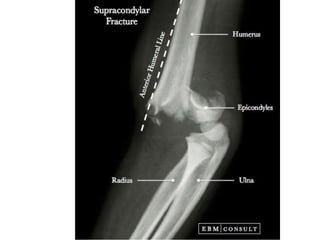

Supracodylar fracture –common and most serious fractures in childhood Mechanism- Fracture is caused by a fall on an out-stretched hand. As the hand strikes the ground, the elbow is forced into hyperextension resulting in fracture of the humerus above the condyles. Extension- Distal fragment is extended(tilted backwards) in relation to the proximal fragment Flexion- the distal fragment is flexed (tilted forwards) in relation to the proximal fragment.